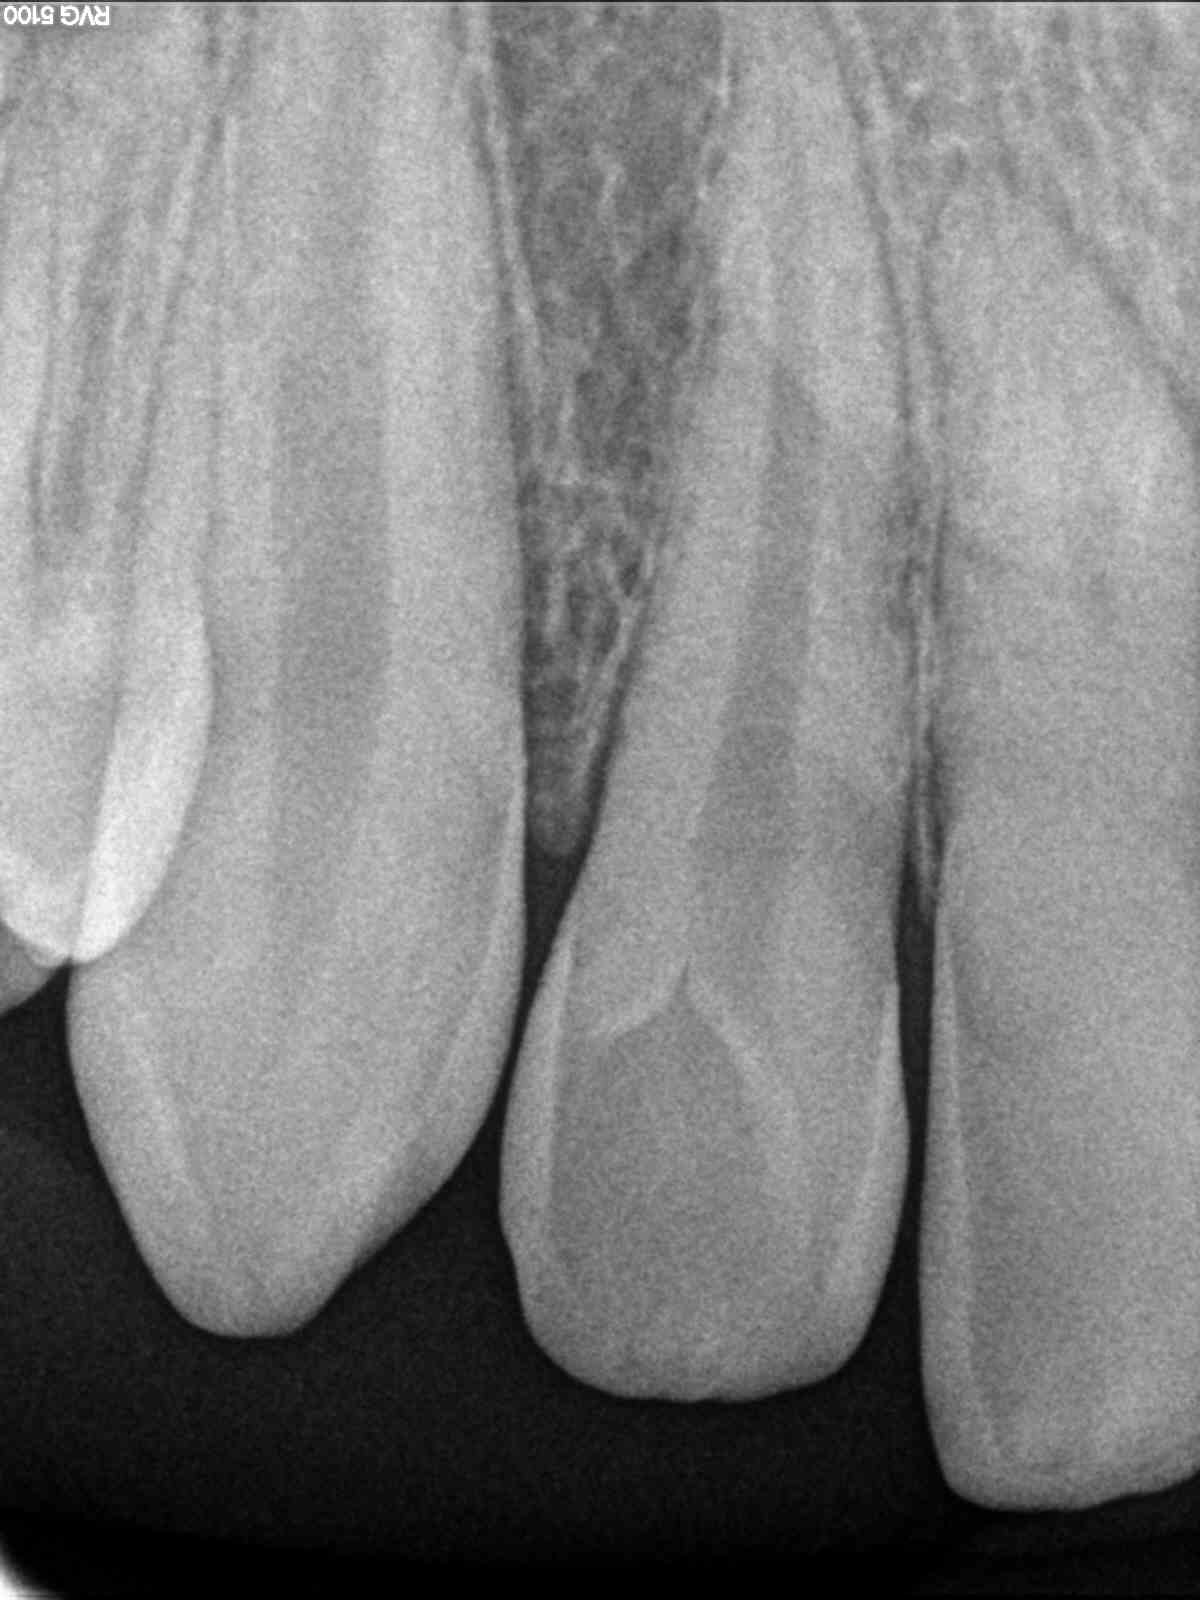

Patient de 13 ans qui consulte après un épisode douloureux qui a disparus.

Potentiellement chute à 7-8 ans.

21 arrêt de la production dentinaire.

11 au contraire hyperproduction et fermeture de la lumière canalaire.

21 arrêt de l’édification radiculaire. Ca va se finir avec une nécrose et un cône moulé.

11, il va falloir forer bien pour trouver le nerf.

Elle sera à dévitaliser un jour. Aujourd'hui peu être pas, mais tu as sur les deux racines les conséquences d'un choc.

Ces dents méritent déjà un suivis qui n' a pas été fait en premier lieu. Mais la nécrose arrivera.